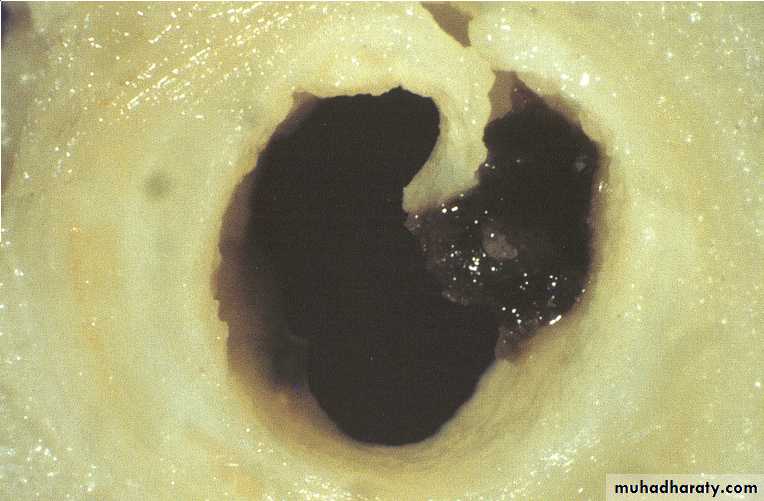

Unstable angina with

plaque disruptionused with permission from M.J. Davies

Unstable angina with plaque disruption

The plaque cap is torn,

projects into the lumen, exposing a mass of thrombus filling the lipid coreDevelopment of Atherosclerotic Plaques